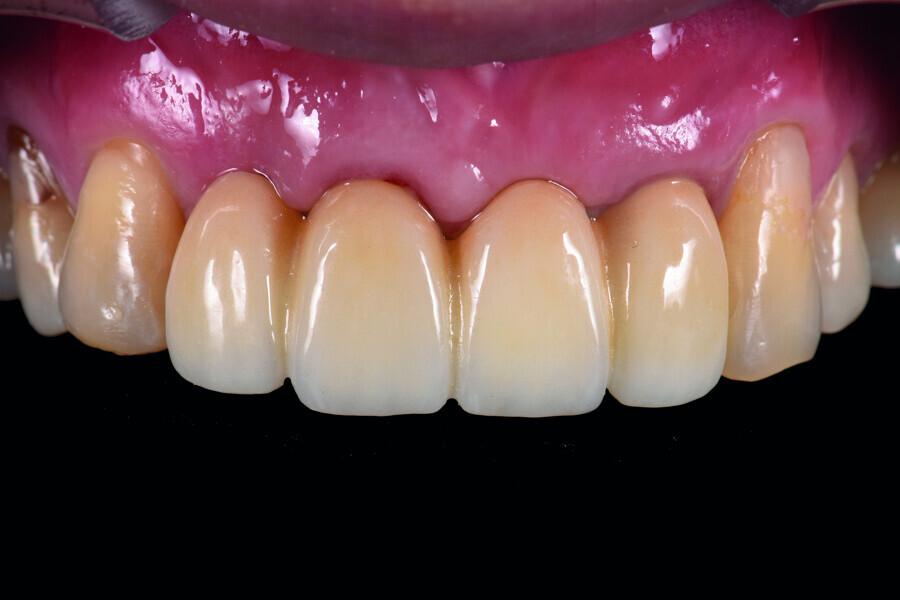

Fig. 43: Frontal view of the anterior teeth just after delivery.